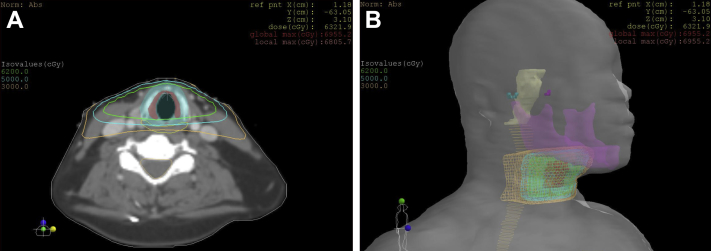

The patient was treated with definitive radiation therapy to the larynx and received a total dose of 62 Gy in 31 fractions of 2 Gy each delivered once daily using 6-MV photons, per our departmental policy. The total treatment duration was 50 days, including breaks and weekends. After she received 14 Gy, she had a treatment break of 10 days because she was hospitalized at an outside facility for a gastrointestinal bleed. She then completed treatment as planned. Right and left posterior oblique fields were used, with gantry angles of 260° and 100°, respectively. Thirty-degree wedges were used to reduce anterior hotspots. The field sizes were 5.7 cm superior to inferior and 4.6 cm anterior to posterior. No bolus was used throughout the course of radiation therapy. The dosimetry is shown in Fig 1.

Figure 1.

Dosimetry. (A) Representative axial sections showing isodose lines. Green = 62 Gy, cyan = 50 Gy, orange = 30 Gy. (B) Three-dimensional rendering of isodose lines. Mandible is purple, spinal cord is light orange, and brain stem is yellow.